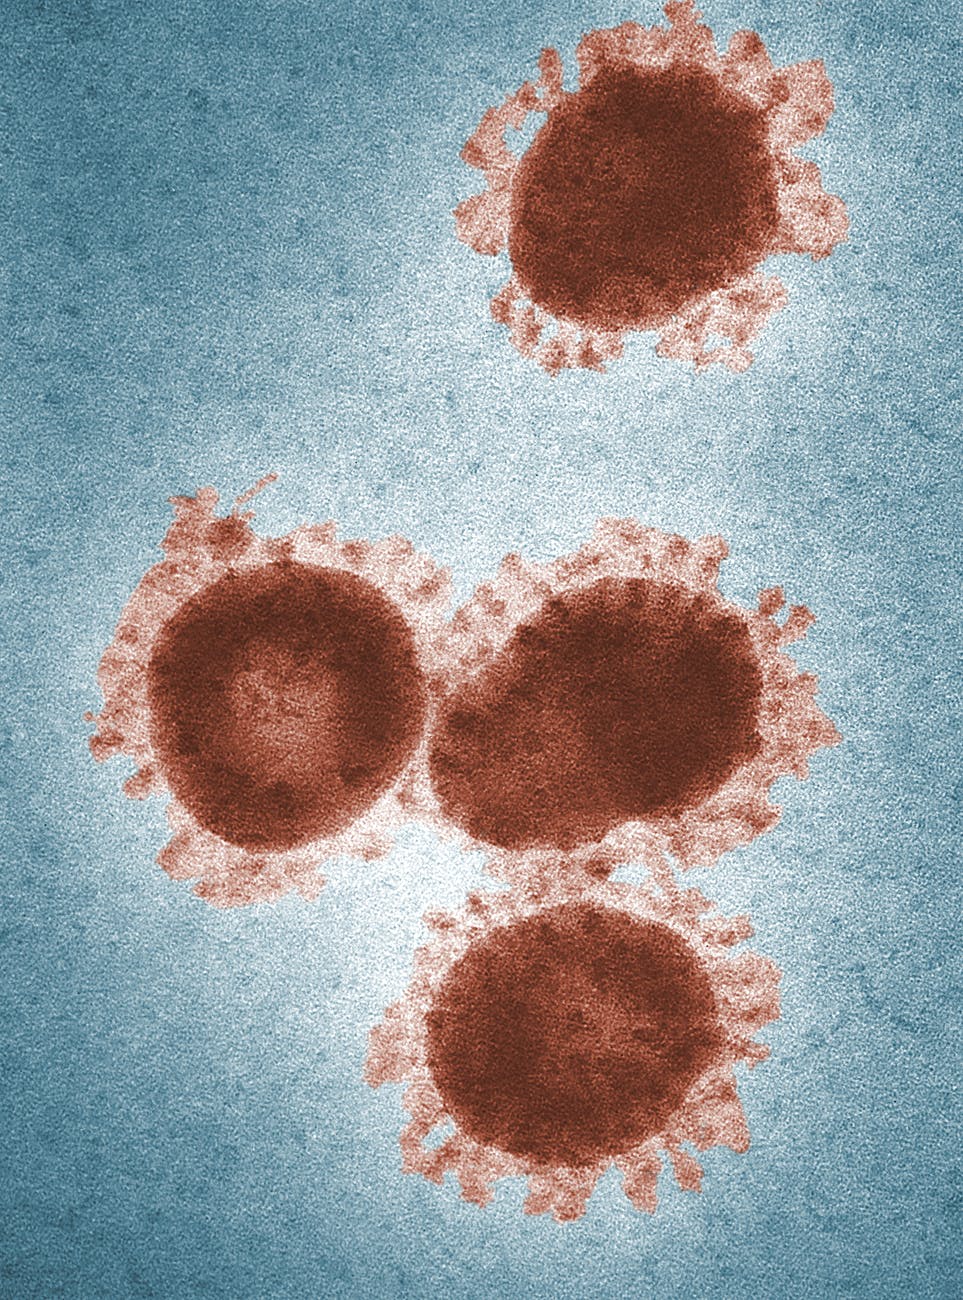

¿Qué es la influenza H1N1?

La influenza H1N1 es una enfermedad respiratoria que afecta a la nariz, garganta y pulmones. Es causada por los virus de la influenza común (gripe).

El virus de la gripe influenza H1N1 se remonta al año 2009. El primer caso registrado fue el de un niño de 10 años de edad, en la ciudad de México. Según reportes de la Organización Mundial de la Salud (OMS) y del Centro de Control y Prevención de Enfermedades (Centers for Disease Control and Prevention, CDC, en inglés) se reportó la presencia de un virus de característica genética muy rara.

La razón fue que este virus era transmitido de los cerdos hacia los humanos sin ningún indicador del origen genético. Del mismo modo, en 2009 se reportó, a nivel global, que al menos el 87% de las muertes por influenza H1N1 ocurrieron en niños, así como en personal sanitario que trabajaba en instancias hospitalarias. La tasa de mortalidad reportada fue de 4:7 en adultos y de 8:12 en niños (Sundar et al., 2011).